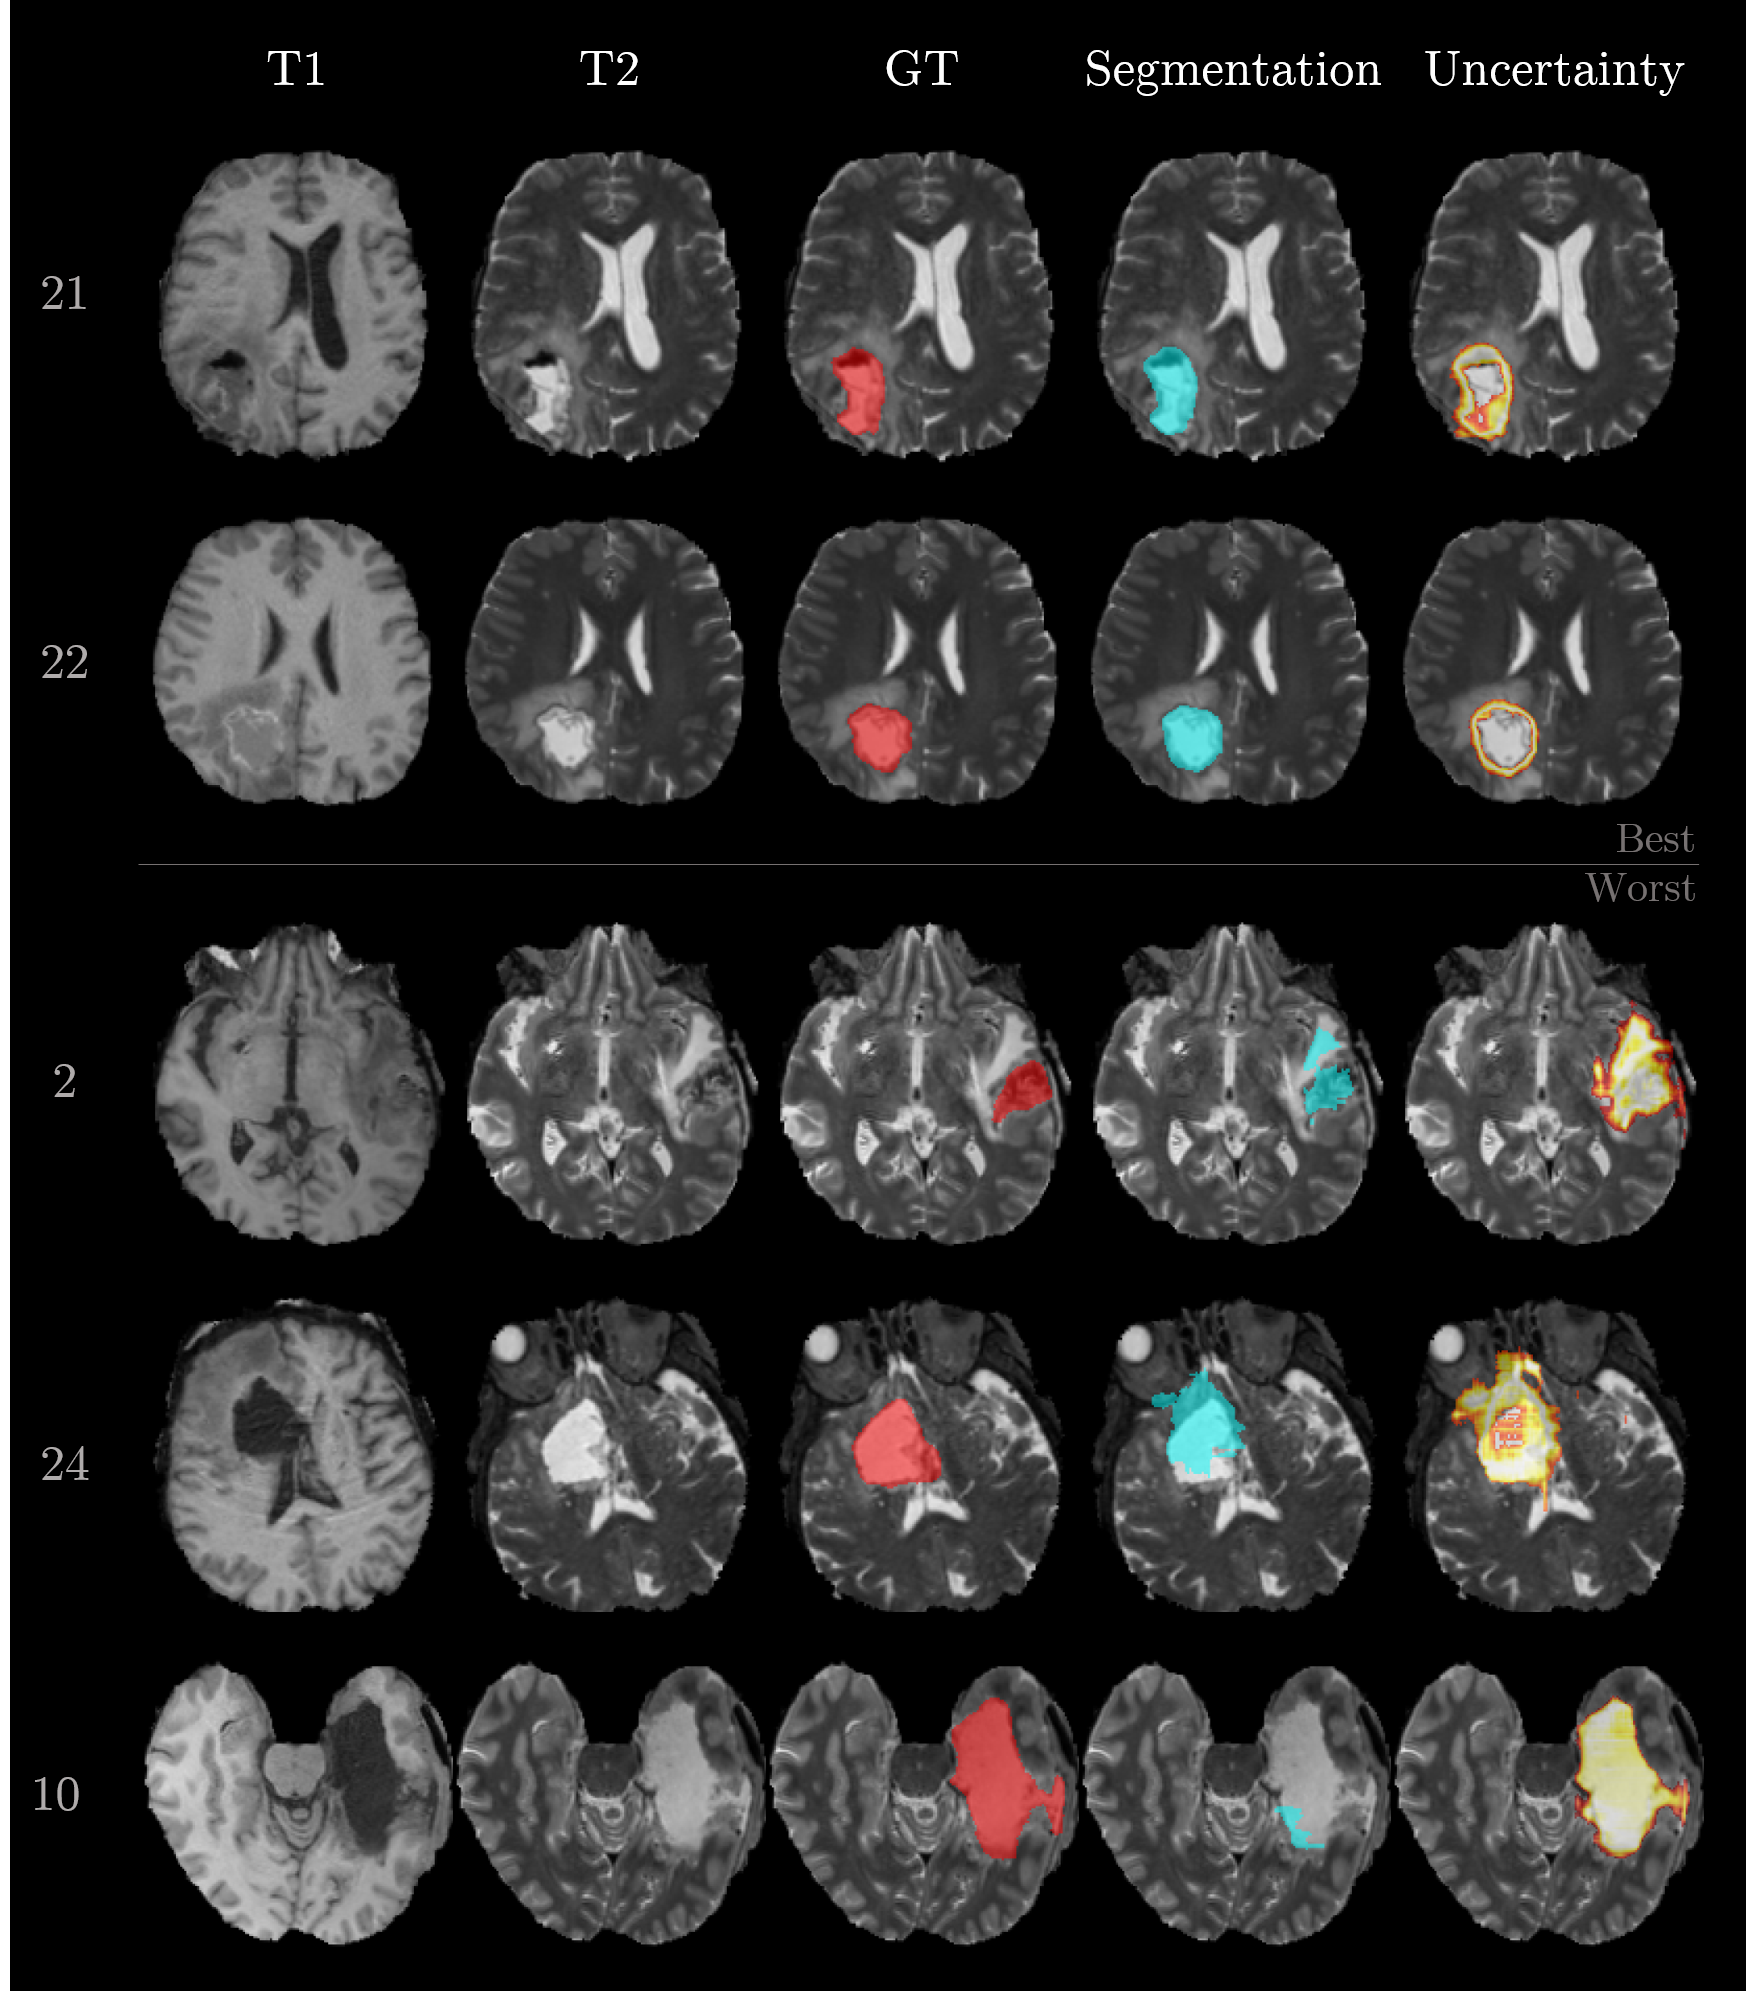

Figure 3 visualizes the segmentation results for the selected samples. The first and second row correspond to the best-performing cases. Their segmentation is close to ground truth and the uncertainty is mainly present at the boundary between foreground (i.e., cavity) and background. In contrast, samples 2, 24, and 10 show the worst performances. The network is struggling with the inhomogeneous cavity of sample 2. There is no clear delineation in the input sequences, which makes the task difficult. Sample 24 is most probably flawed because of the erroneous registration (compare T1 and T2 in Figure 3). Sample 10 is failing although the cavity is clearly visible in the T1 and T2 sequence. Further analysis of this case pointed to a particular hypointense cavity in the FLAIR sequence which appears isointense to cerebrospinal fluid and might confuse the network. Additionally, all three cases yielded increased uncertainties.

Refer to caption

Figure 3: Exemplary cases of segmented postoperative brain tumor cavities. The row numbers on the left correspond to the sample number. The two top rows show the best performing cases and the three bottom rows the worst cases. Columns represent the type of information (input sequences T1 and T2, ground truth (GT), and the network outputs, i.e., segmentation and uncertainty). The input sequences T1c and FLAIR are omitted.

Figure 4 shows the relation between the doubt score and Dice coefficient for the 30 samples of the dataset. The orange horizontal line represents a possible threshold value for the sanity check (e.g. pre-defined by the expert). Every case above the threshold would be flagged as particular error-prone and would require specific review by a clinician. We add another threshold (0.750.750.75) on the Dice coefficient (dashed green vertical line in Figure 4) to separate the good segmentation from the ones that would require improvement. In terms of uncertainty, both thresholds together form regions of true positives (upper left quadrant), false positives (upper right quadrant), false negatives (lower left quadrant) and true negatives (lower right quadrant). The majority of the samples (22 out of 30) are situated either in true positives (4 samples) or the true negatives (18 samples).

In addition to the qualitative examples in Figure 3, Figure 5 focuses on examples situated in the false positives quadrant (sample 3 and 17) and false negatives quadrant (sample 17). The massive brain shift of sample 3 (top row in Figure 5) does not cause the segmentation to fail but is resulting in an increased uncertainty. Likewise, the uncertainty is increased at the meninges and subarachnoid space for sample 27. Both cases lead to large doubt scores because of the high uncertainties located far away from the segmented cavity. In contrast, sample 17 does mainly show uncertainty around the erroneous segmentation which leads to a small doubt score.

Figure 4: Relation between the doubt score and Dice coefficient. The orange horizontal line represents a possible threshold value for the sanity check, and the dashed green vertical line corresponds to a threshold for good segmentation performance. Together they form quadrants of true positives (upper left), false positives (upper right), false negatives (lower left) and true negatives (lower right).

Figure 5: Examples of segmented postoperative brain tumor cavities. The row numbers on the left correspond to the sample number. The two top rows correspond to samples with high doubt scores and Dice coefficients (false positives). The bottom row corresponds to a sample with low doubt score and Dice coefficient (false negative).